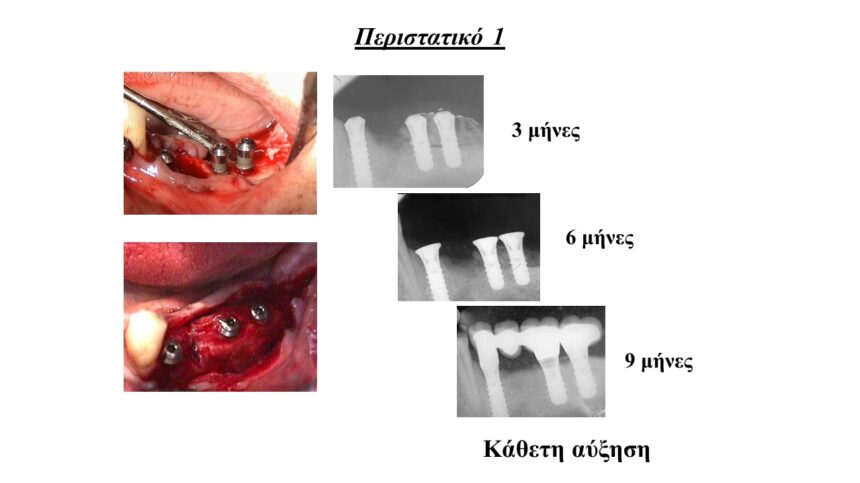

Τρισδιάστατη οστική ανάπλαση της ακρολοφίας με χρήση απορροφήσιμων , μη απορροφήσιμων μεμβρανών και μοσχευμάτων. Ενδείξεις, αντεδείξεις, πλεονεκτήματα - μειονεκτήματα.

Μεταξύ των επεμβάσεων - εφόσον υπάρχει χρόνος - θα παρουσιαστούν περιστατικά, ολοκληρωμένα από 20ετίας, τα οποία θα περιλαμβάνουν όλα τα παραπάνω ( τη χρήση μεμβρανών, PRF και ανύψωση της μεμβράνης ιγμορίου.